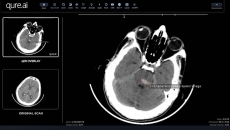

They will deploy AI to help reduce delays and gaps in stroke care management.